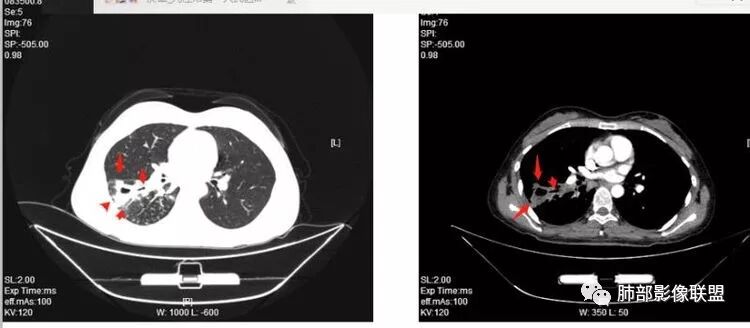

年轻女性:右肺下叶背段,基底段不规则厚壁空洞,内壁光滑,且内壁上有坏死组织,第一次有液气平面,边缘分叶、膨隆、平直,周围多发腺泡结节,树芽,内侧支气管有狭窄。抗感染治疗后空洞缩小,但腺泡结节变化不大,考虑:肺结核合并伴感染?

尘缘:这个形态,周围有收缩的胸膜牵拉与引流支气管的改变,都符合典型的结核空洞表现

2.右肺下叶片状影、结节影、硬树丫。单发空洞伴液平,内壁规则,外壁较清楚。相关支气管壁增厚。

影像符合典型继发性肺结核,或者说结核它是之前已经存在的。